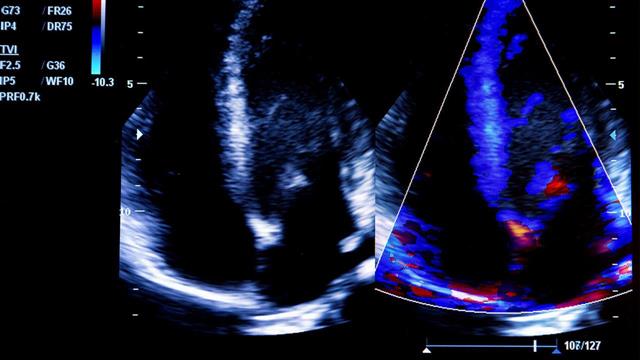

Περίπου το 42% των ασθενών με καρδιακή ανεπάρκεια είχαν διατηρήσει το κλάσμα εξώθησης της αριστερής κοιλίας, το οποίο συμβαίνει όταν ο κάτω αριστερός θάλαμος της καρδιάς (αριστερή κοιλία) δεν μπορεί να γεμίσει σωστά με αίμα (διαστολική φάση), μειώνοντας έτσι την ποσότητα του αίματος που αντλείται πίσω στο σώμα.